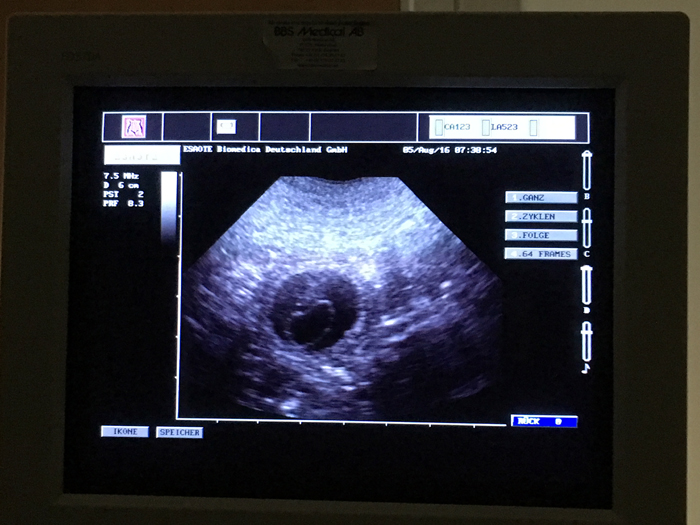

Ultraljud på måndag

På måndag gör vi ultraljud för att se om Fanny har valpar i magen. Håll tummarna!

Lotta är dräktig!!

Vi har gjort ultraljud och det finns många valpar i Lottas mage!! Stolt pappa är Bertil (Actualis Winter Surprise).

Valparna föds i mitten av januari och vill flytta till sina nya familjer i matten av mars.

Det finns många valpar i magen enligt ultraljudet!